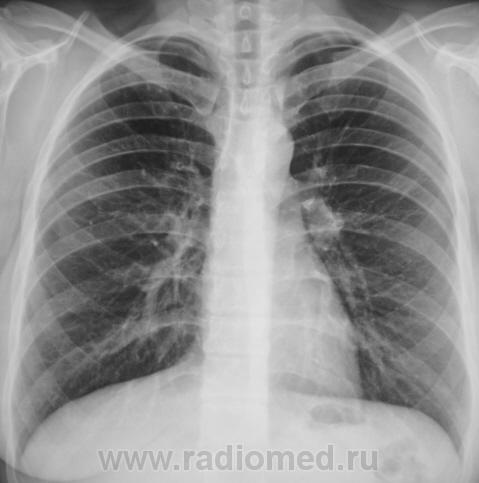

Томограмма верхушки справа (1-2 среза 6-7 см); есть очаг - в работу, нет - значит повезло.....

Ниже томограммы верхушек.

[[wysiwyg_imageupload:723:]][[wysiwyg_imageupload:724:]][[wysiwyg_imageupload:725:]][[wysiwyg_imageupload:726:]]

Томограммы добавлены.

Что и следовало доказать - к фтизиатрам (хотя очег и несколько плотноват...или я не прав?)

Конечно, Вы правы. По прямой дороге потопал пациент к фтизиатру, а фтизиатр принял его, как родного...